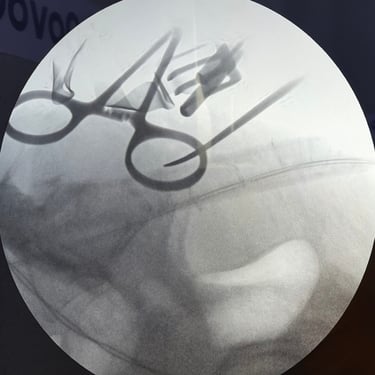

Sarcoma Sacro: Citorreducción Tumoral y Descompresión Nerviosa

El sarcoma sacro es una neoplasia poco frecuente y de manejo complejo que puede generar dolor severo, alteraciones neurológicas y compromiso de la movilidad por afectación de las raíces nerviosas sacras. El tratamiento quirúrgico mediante citorreducción tumoral tiene como objetivo disminuir el volumen del tumor, mientras que la descompresión nerviosa permite aliviar la presión sobre las estructuras neurológicas comprometidas. Este abordaje busca mejorar el control del dolor, preservar la función neurológica y optimizar la calidad de vida del paciente. La planificación cuidadosa y el manejo multidisciplinario son fundamentales para obtener mejores resultados clínicos.